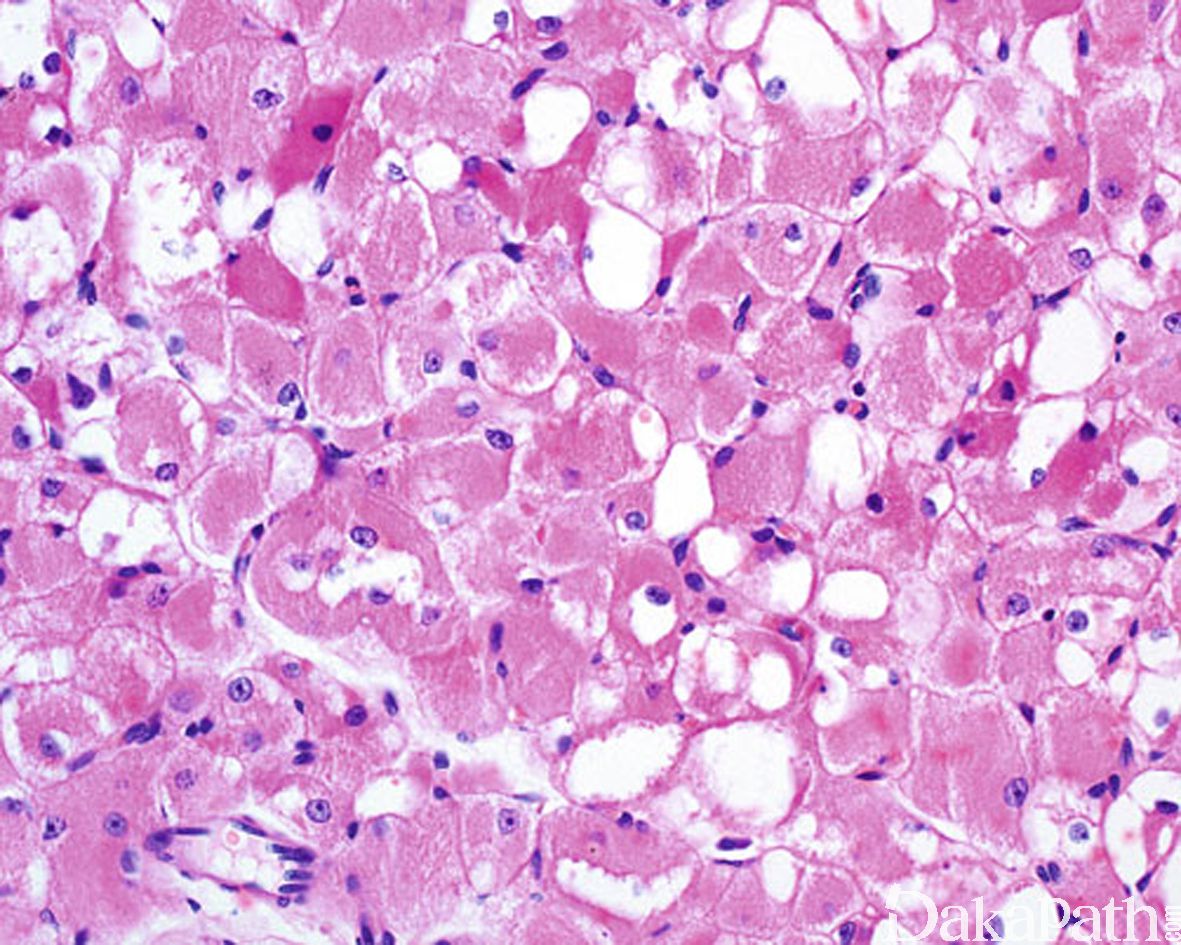

瘤细胞体积大,边界清楚,胞质丰富,嗜伊红色、颗粒状或透亮,有时可见胞浆透亮细胞中央有少量深嗜伊红色的胞质呈细条索状向周边放射伸展,形成所谓的蜘蛛细胞;

部分细胞内可见横纹,或可见棒状或杂草样结晶样物;

瘤细胞的核小、圆形,染色质呈空泡状,可见小核仁,无或罕见核分裂像。